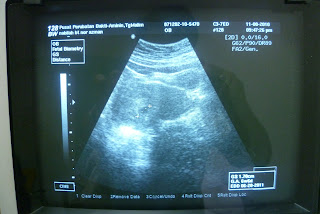

scaNNing baBy...@ Pusat peruBatan Bakti AmiNin

8.11.10